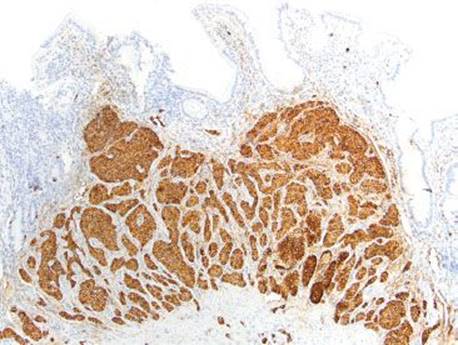

Figure 2.83 Chronic gastritis pattern, well-differentiated neuroendocrine (carcinoid) tumor (type I). Prolonged and unchecked gastrin stimulation of the ECL cells can lead to transformation of ECL cell hyperplasia into neuroendocrine tumors (type I, when in the setting of AMAG). One should always carefully evaluate of the background gastric mucosa in all cases of gastric neuroendocrine tumors to aid in classification, treatment, and prognosis.

Figure 2.84 Chronic gastritis pattern, well differentiated neuroendocrine (carcinoid) tumor (type I) (chromogranin immunostain). Previous case (Fig. 2.83). The distinction between reversible nodular ECL cell hyperplasia and neuroendocrine neoplasm is somewhat arbitrary. The College of American Pathologists suggests a size threshold of ≥0.5 mm for neuroendocrine tumors, whereas smaller nodules are considered ECL cell hyperplasia (or “dysplasia”).